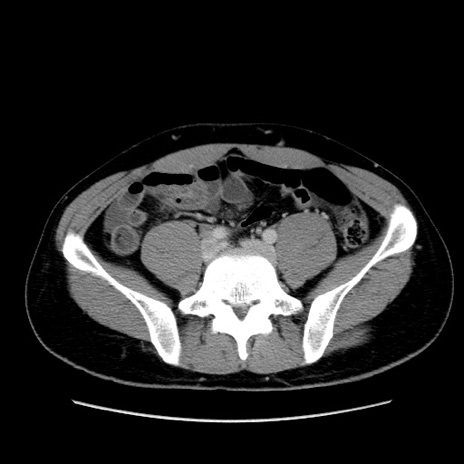

症例36(横断像)

【症例】20歳代 男性

【主訴】心窩部痛

【現病歴】今朝より上腹部痛あり。一旦軽快していたが再度出現したため救急要請。昨日夕に白身の魚を含む刺身を食べた。

【身体所見】BP 136/89mmHg、HR 74/min、BT 37.0℃、腹部:膨満、軟、心窩部に圧痛あり。反跳痛なし、筋性防御なし、腸雑音やや亢進あり。

【データ】WBC 17700、CRP 0.48